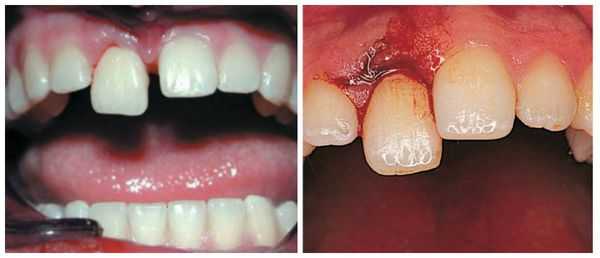

При полном вывихе (авульсии, травматической экстракции зуба) происходит разрыв всех периодонтальных тканей и круговой связки зуба, что сопровождается его выпадением из лунки. Чаще наблюдается полный вывих центральных резцов верхней челюсти. Стоматологический осмотр выявляет отсутствие зуба в зубном ряду, наличие на его месте пустой лунки со свежим сгустком крови или признаками продолжающегося кровотечения. При травмах зубов, сопровождающихся их вывихом, нередко имеются ушибы и раны мягких тканей лица, губ, слизистой полости рта.

Слизистая оболочка в области зуба 1.6 физиологической окраски, безболезненная при пальпации. Сам зуб находится под пломбой, занимающей более 2/3 коронки. На нёбной поверхности зуба виден дефект, широко сообщающийся с полостью зуба, при его зондировании возникает боль. В области дефекта есть пародонтальный карман (пространство между десной и зубным корнем) более 4 мм. Определяется поперечная линия перелома нёбного корня ниже уровня десны на 3 мм. Сам нёбный корень в лунке подвижен, при этом щёчные корни остаются неподвижными. Перкуссия (постукивание) зуба 1.6 болезненная. Противоположный жевательный зуб 4.6 находится под металлической коронкой. Пациент направлен на прицельный внутриротовой рентгеновский снимок зуба. Из-за особенностей прицельной рентгенограммы, наложения структур друг на друга и наличия снимка только в одной проекции линия перелома нёбного корня зуба 1.6 определяется недостаточно чётко. Но в связи с наличием явных клинических признаков, указывающих на перелом корня зуба, принято решение о его удалении.